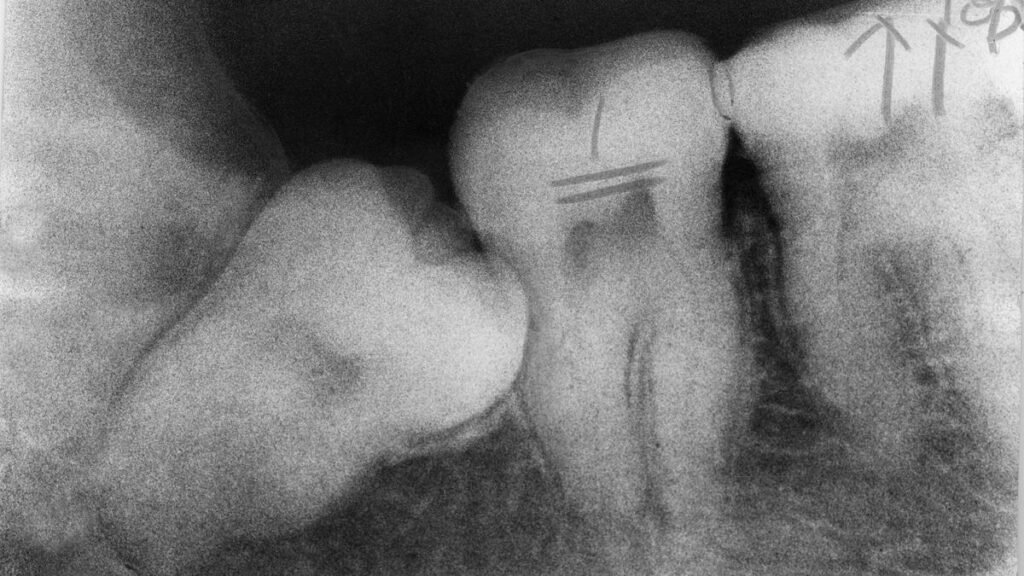

Most people are born with no teeth showing in their mouths at all, even though your baby teeth start developing before you’re even born. Baby teeth usually start poking through the gums when you’re between 6 and 8 months old. Sometimes when dentists take X-rays to check for cavities or other problems, they can see adult teeth growing within the gums.